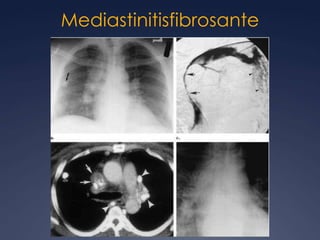

Mediastinitisfibrosante

MediastinitisfibrosanteRadioGraphics 2001; 21:737-757